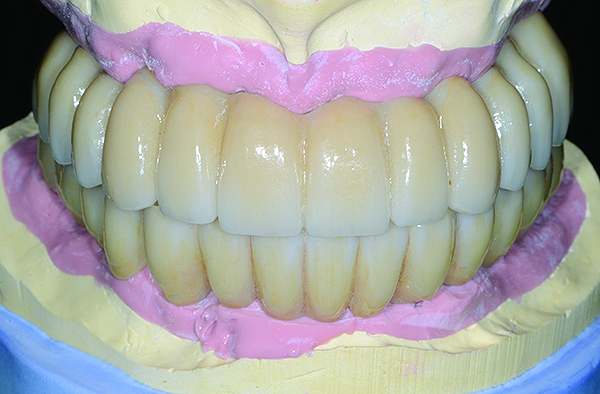

The maxillary prototype was adjusted, polished, and left to function with the mandibular provisional. The definitive maxillary zirconia restoration was then completed from the information provided by the prototype, and the cutbacks for the facial porcelain (Nos. 6 through 11) were done after milling but before sintering. Subsequently, the mandibular prototype was adjusted to the sintered and colored maxillary zirconia framework before the application of porcelain to Nos. 6 through 11 and final glazing (Figure 11). Following this step, the mandibular definitive monolithic zirconia restoration was milled, colored, and sintered. The facial porcelain (Nos. 6 through 11) was applied, and then both maxillary and mandibular restorations were stained and glazed (Figure 12). Both bridges were inserted at the same time (Figure 13 through Figure 15). Minor occlusal adjustments and oral hygiene access was verified and the zirconia surfaces polished. The bridge screws were torqued to 20 Ncm according to the manufacturer’s recommendation, and No. 24 was luted with a provisional cement. Postoperative radiographs were taken (Figure 16).

Fig 12. Extraoral frontal view of the completed maxillary and mandibular articulated zirconia restorations on master casts.

Figure 12